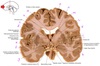

1

Q

a

body of corpus callosum

2

b

Anterior horn of lateral ventricle

3

c

Septum pellucidum

4

d

Rostrum of corpus callosum

5

e

Head of caudate nucleus

6

f

Anterior limb of internal capsule

7

g

Putamen

8

h

Nucleus accumbens